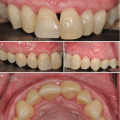

Fig. 5.1

Gingiva–anatomic crown relationship. Type I – the gingival margin is located incisal to the cementoenamel junction, and the gingival dimension is prominently wider from the margin to the mucogingival junction (a, b). Type II – normal dimension of the gingival margin to the mucogingival junction (c, d)